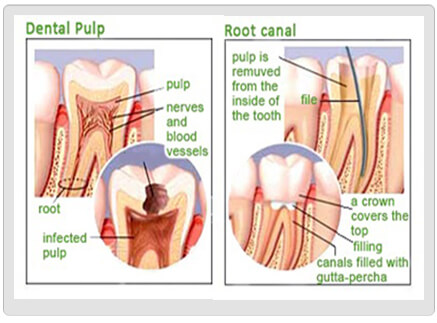

Case of the month: Root Canal Treatment Middle age women reported to the US DENTAL CLINIC with a chief complaint…

WHAT IS A SINGLE VISIT ROOT CANAL TREATMENT? AM I A CANDIDATE FOR IT? Mostly we all have experienced the…

Common Questions Answered About Root Canal Treatment Some people might have questions in mind before booking a dental appointment whether…